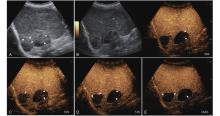

Figure 17

LR-TR Nonevaluable. Example of a treated tumor 22 days after TACE. (A) B-mode image shows a slightly hyperechoic target lesion measuring 24 mm in segment IV; (B) CEUS shows mild hypoenhancement of the lesion at 14 s during the arterial phase; (C) A non enhancing lesion measuring 16 mm on US distinct from the target lesion is observed at 24 s of the arterial phase; (D) The lesion is not visualized in the portal venous phase. This finding represents inadequate arterial-phase coverage and is defined as a nonevaluable lesion."